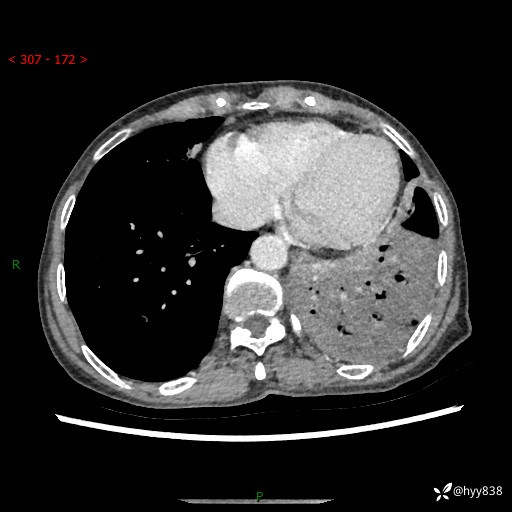

胸部CT平扫+增强